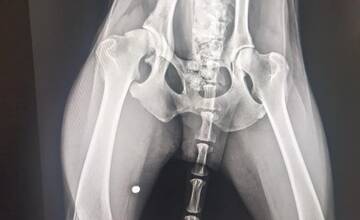

FOTO: Utýraný a vyhladovaný Odin mal v tele starší brok

FOTO: V tele týraného psíka našli brok. Previezli ho do bratislavskej Slobody zvierat